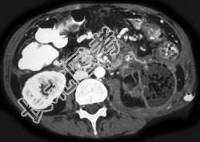

- 单项选择题女性,34岁, 寒战、高热、急性中上腹偏左腹痛,压痛, CT扫描如图,最可能的诊断是 ( )

A、急性胰腺炎

B、胰腺脓肿

C、慢性胰腺炎急性发作

D、胰腺癌

E、胰腺转移癌